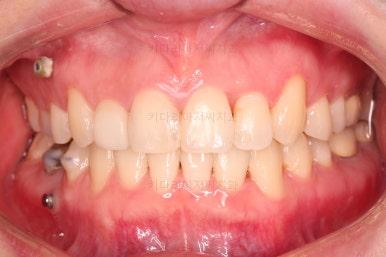

부산치과교정 전후사진을 비교해 볼게요.

발치교정이라고 입매가 들어간 것도 아니고 오히려 더 예뻐졌죠?

중심선도 원하시는만큼 갖추었고, 가지런한 느낌도 좋고요.

21개월만에 전반적으로 매우 만족할만한 치료 결과를 얻었습니다.